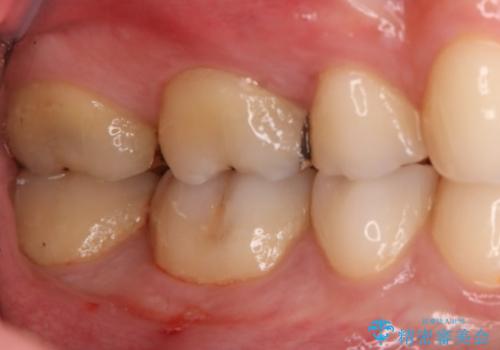

- 右下6・7番の虫歯治療を主訴に来院された患者様です。

精度が高く見た目が良いものを希望されたので、切削量・形態を考慮しセラミックインレーでの治療を計画しました。

奥歯でも下の歯の場合は審美性の高いセラミックを選択される患者様が多いです。